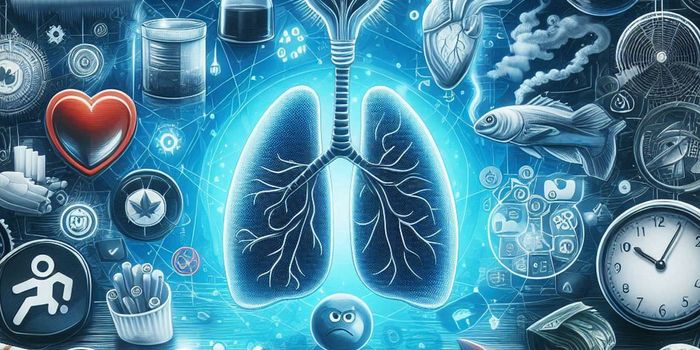

FEB 06, 2025Cannabis SciencesCannabis use is linked to greater chances of having asthma, according to a recent systematic review and meta-analysis.